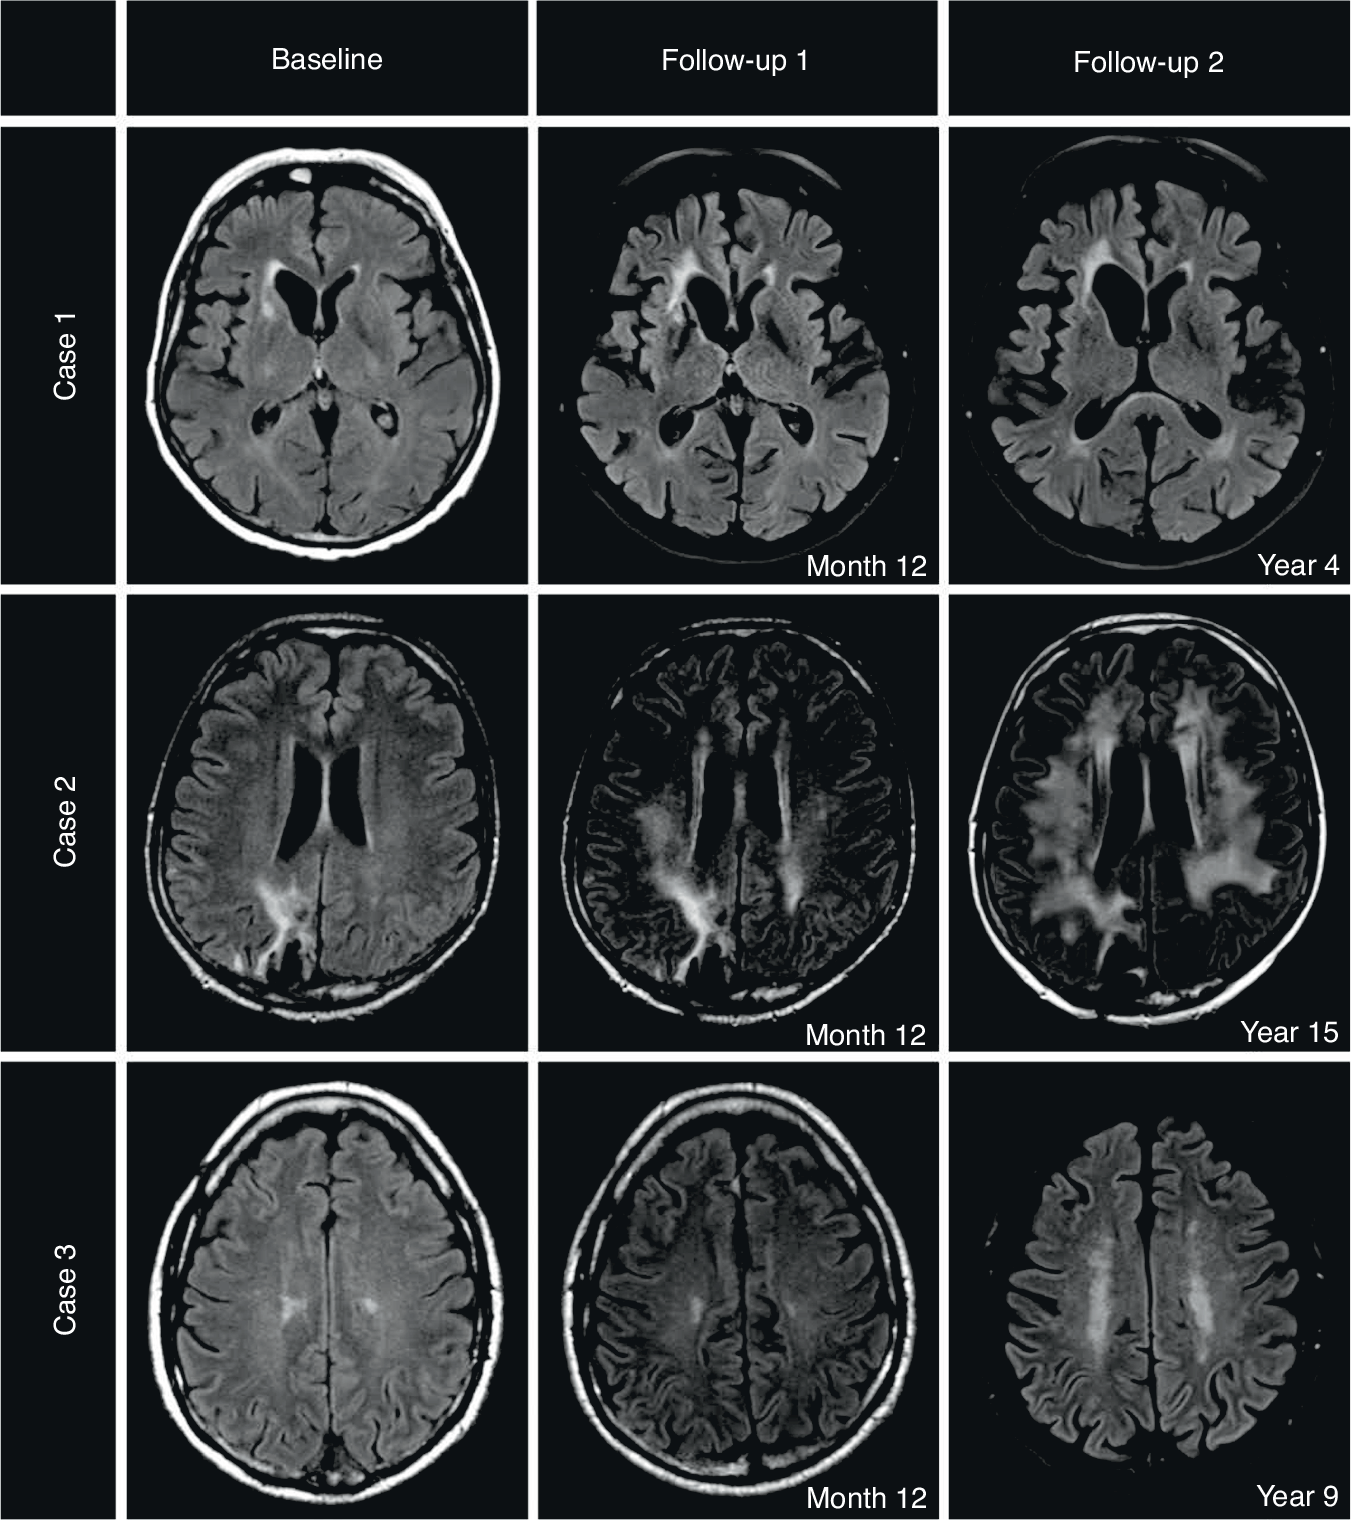

Fig. 3: Exemplary Time Courses of 3 PCNSL cases.

Case 1: Normal brain aging in a female PCNSL patient, 63 years at diagnosis with a 4-year follow-up period. Low WML burden at baseline (score 0) and at latest follow-up (score 1). Neurocognitive status at year 4: ECOG 0, MMSE 30 points, GHS unknown, QoL subscales all >80%. Case 2: Early WML changes in a male PCNSL patient, 43 years at diagnosis with a 15-year follow-up period. Low WML burden at baseline (score 0) with early conversion to high WML burden at month 12 (score 2). The high WML burden persisted until year 15 (score 3 from month 36 onwards). Neurocognitive status at year 15: ECOG 0, MMSE 28 points, GHS 50%. Case 3: Late WML changes in a male PCNSL patient, 60 years at diagnosis with a 9-year follow-up period. Low WML burden at baseline (score 1) with late conversion to high WML burden at month 60 (score 2). The high WML burden persisted unchanged until year 9 (score 2). Neurocognitive status at year 9: ECOG 0, MMSE 28 points, GHS 91.67.